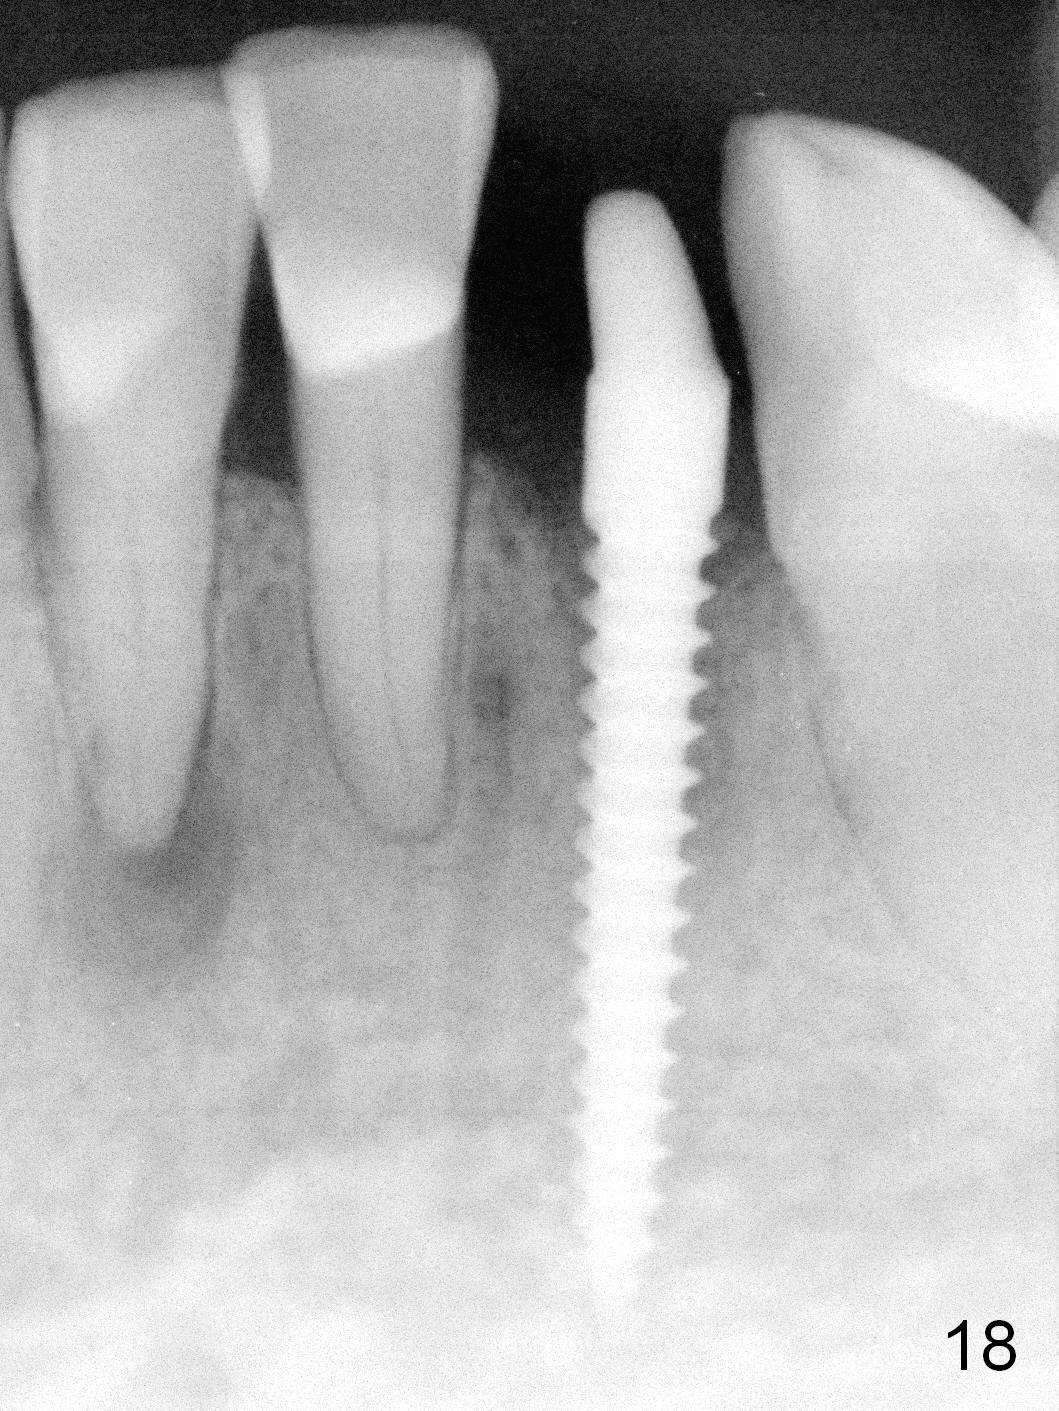

Five months postop, the peri-implant space reduces (Fig.18).  A keratinized band forms buccal to the implant (Fig.19 *).  The provisional dislodges probably due to the buccal placement (Fig.20).